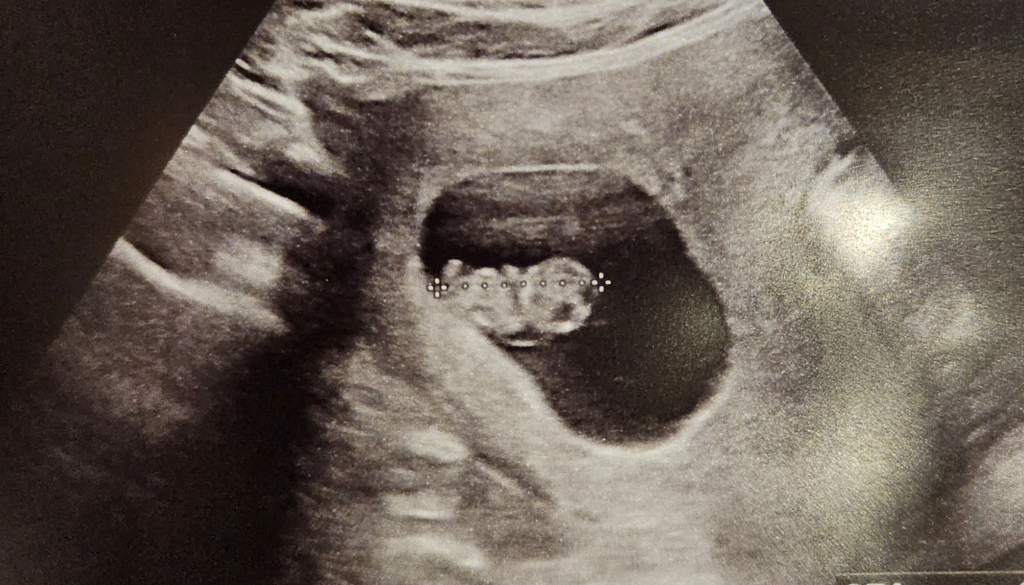

아직은 하리보 곰젤리

결혼한 지 5년이 넘었고 오랜 기간 아이를 기다려왔음에도 막상 임신을 하니 실감이 나지 않는다. 주변 많은 사람들이 응원해주었고, 회사 동료들은 일보다 몸을 먼저 생각하라고 늘 이야기해 주어서 정말 고마웠다. (내가 임신했다는 얘기를 듣고 눈물을 흘린 동료도 있었다.) 30대 후반에 접어들었으나, 아직 아이를 낳지 않은 여자들은 혼인 여부와 관계없이 임신에 대한 고민을 한다. 물리적인 시간이 얼마 남지 않았다는 생각에 괴롭고, 그럼에도 당장 할 수 있는 일이 없다는 사실에 막막하다.

올해 본격적으로 임신을 준비하며 느낀 것은 그간 살아오며 해왔던 다른 도전들과는 성격이 다르다는 거다. 시험 준비나 취업은 열심히 하면 한 만큼 성과가 가시적이고, 서류 통과든 면접 탈락이든 단계마다 결과물을 받게 되지만 임신은 아니다. 임신이고, 아니면 말고인데 내 몸에 무슨 일이 일어나는지 당최 알 수가 없고, 열심히 한다고 되는 일도 아니다. 마음을 편하게 먹고 스트레스받지 말라고 하는데 그것만큼 어려운 일도 없다. 스트레스를 받을까봐 늘 노심초사하고 오히려 그 사실 때문에 더 스트레스를 받는 아이러니다.

임신을 확인하고 나서는 나의 담당 파트너에게 연락해 프로젝트를 그만두겠다고 했다. 잠시 쉬면서 임신 초기 건강을 챙기고, 임신 중기에 복직을 할 생각이다. 다행히 파트너는 축하해 주면서 건강을 가장 먼저 챙기라며 대체자를 구해줬다. 1년 가까이 해온 프로젝트고 인수인계 할 것들도 많아 프로젝트 오프까지 3주 정도 걸리기는 했지만, 재택근무를 하는 등 동료들이 배려해 주어 무사히 잘 끝낼 수 있었다.

2024년 1월 현재는 인생 최초의 휴직 중이다. 무급 휴직이라 주머니 형편은 나쁘지만 그 어느 때보다 마음이 편하고 평화롭다. 집에만 있으면 무료하고 생산적인 일을 하기 위해 노력할 줄 알았으나 늦잠을 자고 게으름을 피우고 빈둥거리기만 해도 시간은 잘 가고, 집 밖의 세상은 아무 일 없다는 듯이 잘 돌아간다. 직장 생활을 시작한 이래 늘 나를 괴롭혀돈 두통도 말끔하게 사라졌다. 쉬고 나니 비로소 그동안 얼마나 많은 스트레스 상황에 놓여있었는지를 깨닫게 된다.